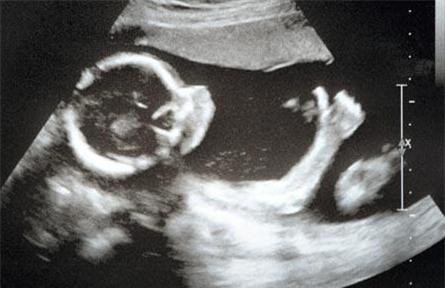

Theo GS.TS Nguyễn Thanh Long, thai phụ sẽ được giám sát chặt khi phát hiện nhiễm Zika. Ảnh: H.Hải

Siêm âm đo chu vi vòng đầu định kỳ sẽ đánh giá được sự phát triển của đầu có bình thường hay bất thường.

“Dù với nguyên nhân nào, thì việc chẩn đoán hội chứng đầu nhỏ không khó khăn, bởi nó hoàn liên quan đến số đo kích thước của đầu và được chẩn đoán chính xác bằng siêu âm. Trong đó giám sát trong 3 tháng đầu mang thai rất quan trọng. Với phụ nữ mang thai 3 tháng đầu được khẳng định nhiễm vi rút Zika dương tính cần được theo dõi sát sao với phác đồ siêu âm đo kích thước chu vi đầu 2 tuần/lần. Bác sĩ sẽ dựa vào biểu đồ phát triển để xem tốc độ phát triển của đầu giảm đi hay bình thường. Nếu tốc độ phát triển bình thường, cho thấy vi rút không gây ảnh hưởng đến thai nhi. Còn nếu tốc độ phát triển của đầu có vấn đề sẽ làm thêm các chẩn đoán để xác định có phải hội chứng não nhỏ do vi rút zika không.

Việc giám sát, phát hiện không có gì phức tạp. Tất cả phụ nữ mang thai đều được khuyến cáo khám thai thông thường. Riêng phụ nữ có thai zika dương tính thì theo dõi chặt 2 tuần/lần bằng siêu âm đo kích thước chu vi đầu, đánh giá tốc độ phát triển để phát hiện”, TS Cường nói.

Cũng theo TS Cường, hiện nay siêu âm là một kỹ thuật chẩn đoán phổ cập, đơn giản. Tại các tuyến xã, huyện đều đã được trang bị máy siêu âm. Các bác sĩ các tuyến từ bắc, trung, nam đã được tập huấn về kỹ thuật phát hiện hội chứng đầu nhỏ bằng siêu âm.

“Các trường hợp có chỉ định giám sát sẽ được theo dõi thai nhi chặt chẽ. Việc siêu âm không phức tạp vì có thể tiến hành đo nhiều lần chu vi vòng đầu. Hơn nữa nếu nghi ngờ kích thước đầu nhỏ chuyển tuyến cao hơn và khi khẳng định hội chứng đầu nhỏ sẽ hội chẩn với các chuyên gia xem tiếp tục hay dừng thai nghén. Vì thế các thai phụ hoàn toàn nên yên tâm với trình độ siêu âm hiện nay”, TS Cường nói.